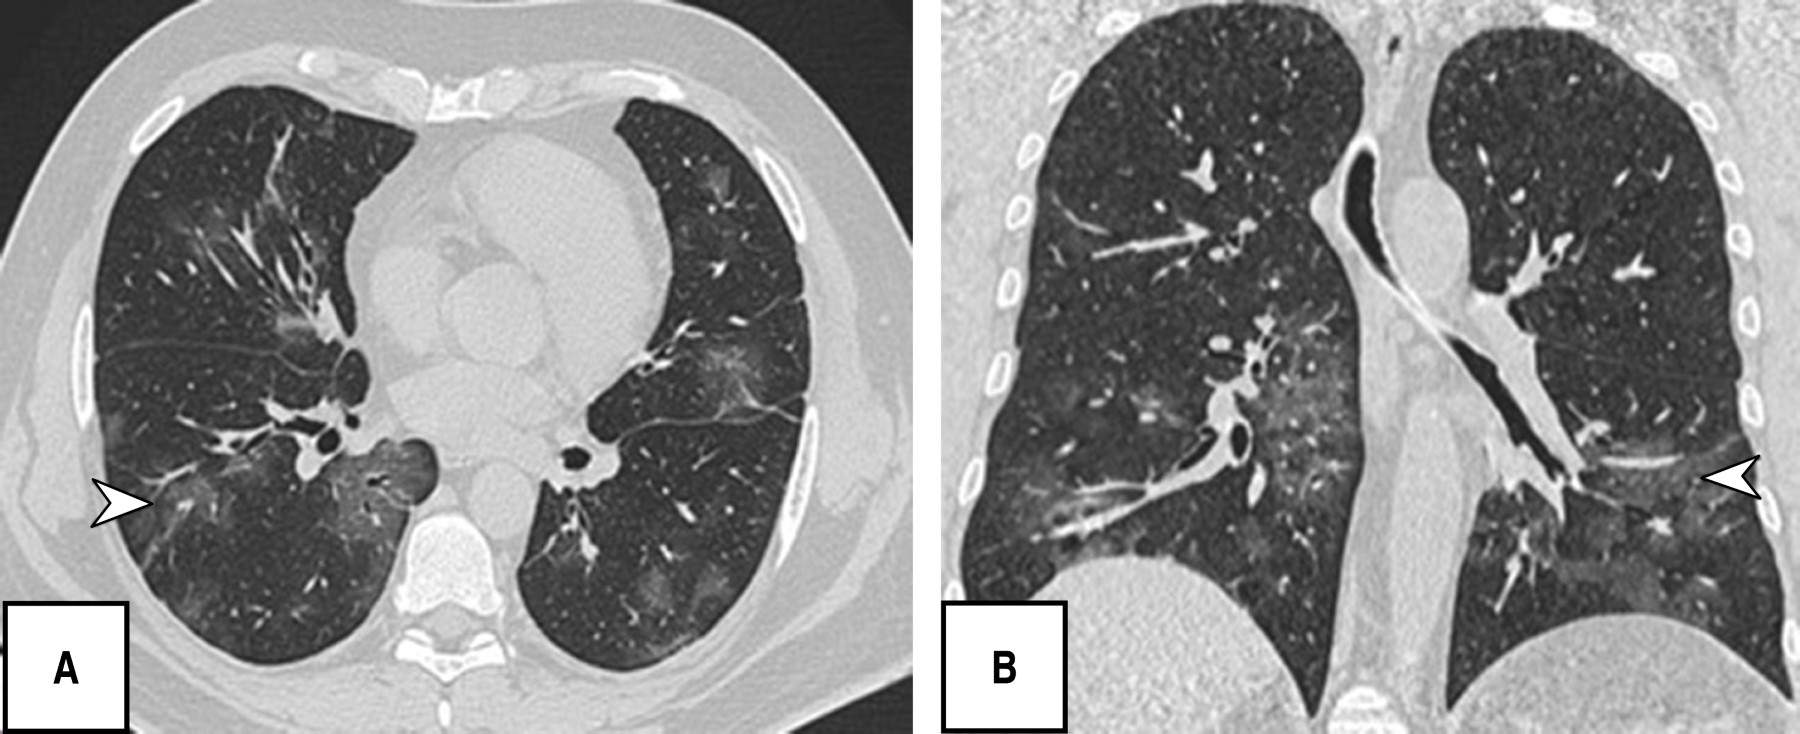

Durante la evaluación tomográfica se obtuvo que los patrones pulmonares más frecuentes fueron: patrón en empedrado (120 [80.5%]), bandas pleuroparenquimales (118 [79.2%]) y patrón en vidrio deslustrado (110 [73.8%]), patrón reticular 82 [55%]), y en menor porcentaje dilatación vascular (56 [37.6%]) y patrón consolidado (52 [34.9%]) (Figuras 1, 2, 3 y 4).

En cuanto a las fases encontradas, la fase de reabsorción se observó con mayor frecuencia (69 [46.3%]) seguida de la fase pico (40 [26.8%]) (Tabla 2).

Es de resaltar que la mayoría de los pacientes en esta investigación se presentaron en una fase crónica/avanzada de la enfermedad encontrando como patrones predominantes el empedrado (120/149; 80.5%), bandas pleuroparenquimales (118/149; 79.5%) y en tercer lugar patrón en vidrio deslustrado (110/149; 73.8%), sin identificar ningún caso con hallazgos de atolón, neumotórax o árbol en gemación, otros estudios sí reportan como hallazgo predominante las opacidades en vidrio deslustrado seguido del patrón en consolidación y al respecto el derrame pleural, derrame pericárdico, linfadenopatía, cavitación, el halo reverso o signo del atolón y neumotórax son poco frecuentes, pero pueden observarse con la progresión de la enfermedad.19-21

Soriano et al. reportaron que la presencia de opacidades en vidrio deslustrado, el patrón reticular, el patrón en empedrado, las líneas subpleurales, el engrosamiento pleural y la fibrosis se encontraron con mayor frecuencia en la fase intermedia/progresiva, especialmente en la fase avanzada; de forma similar observamos una correlación significativa (índice de Pearson de 0.65) entre el patrón predominante y la fase evolutiva de la enfermedad.23 Los puntajes de la TC del grupo de etapa progresiva fueron significativamente mayores que los del grupo de etapa temprana; sin embargo, en este estudio no hubo significancia estadística entre en patrón de TC y el puntaje de severidad.